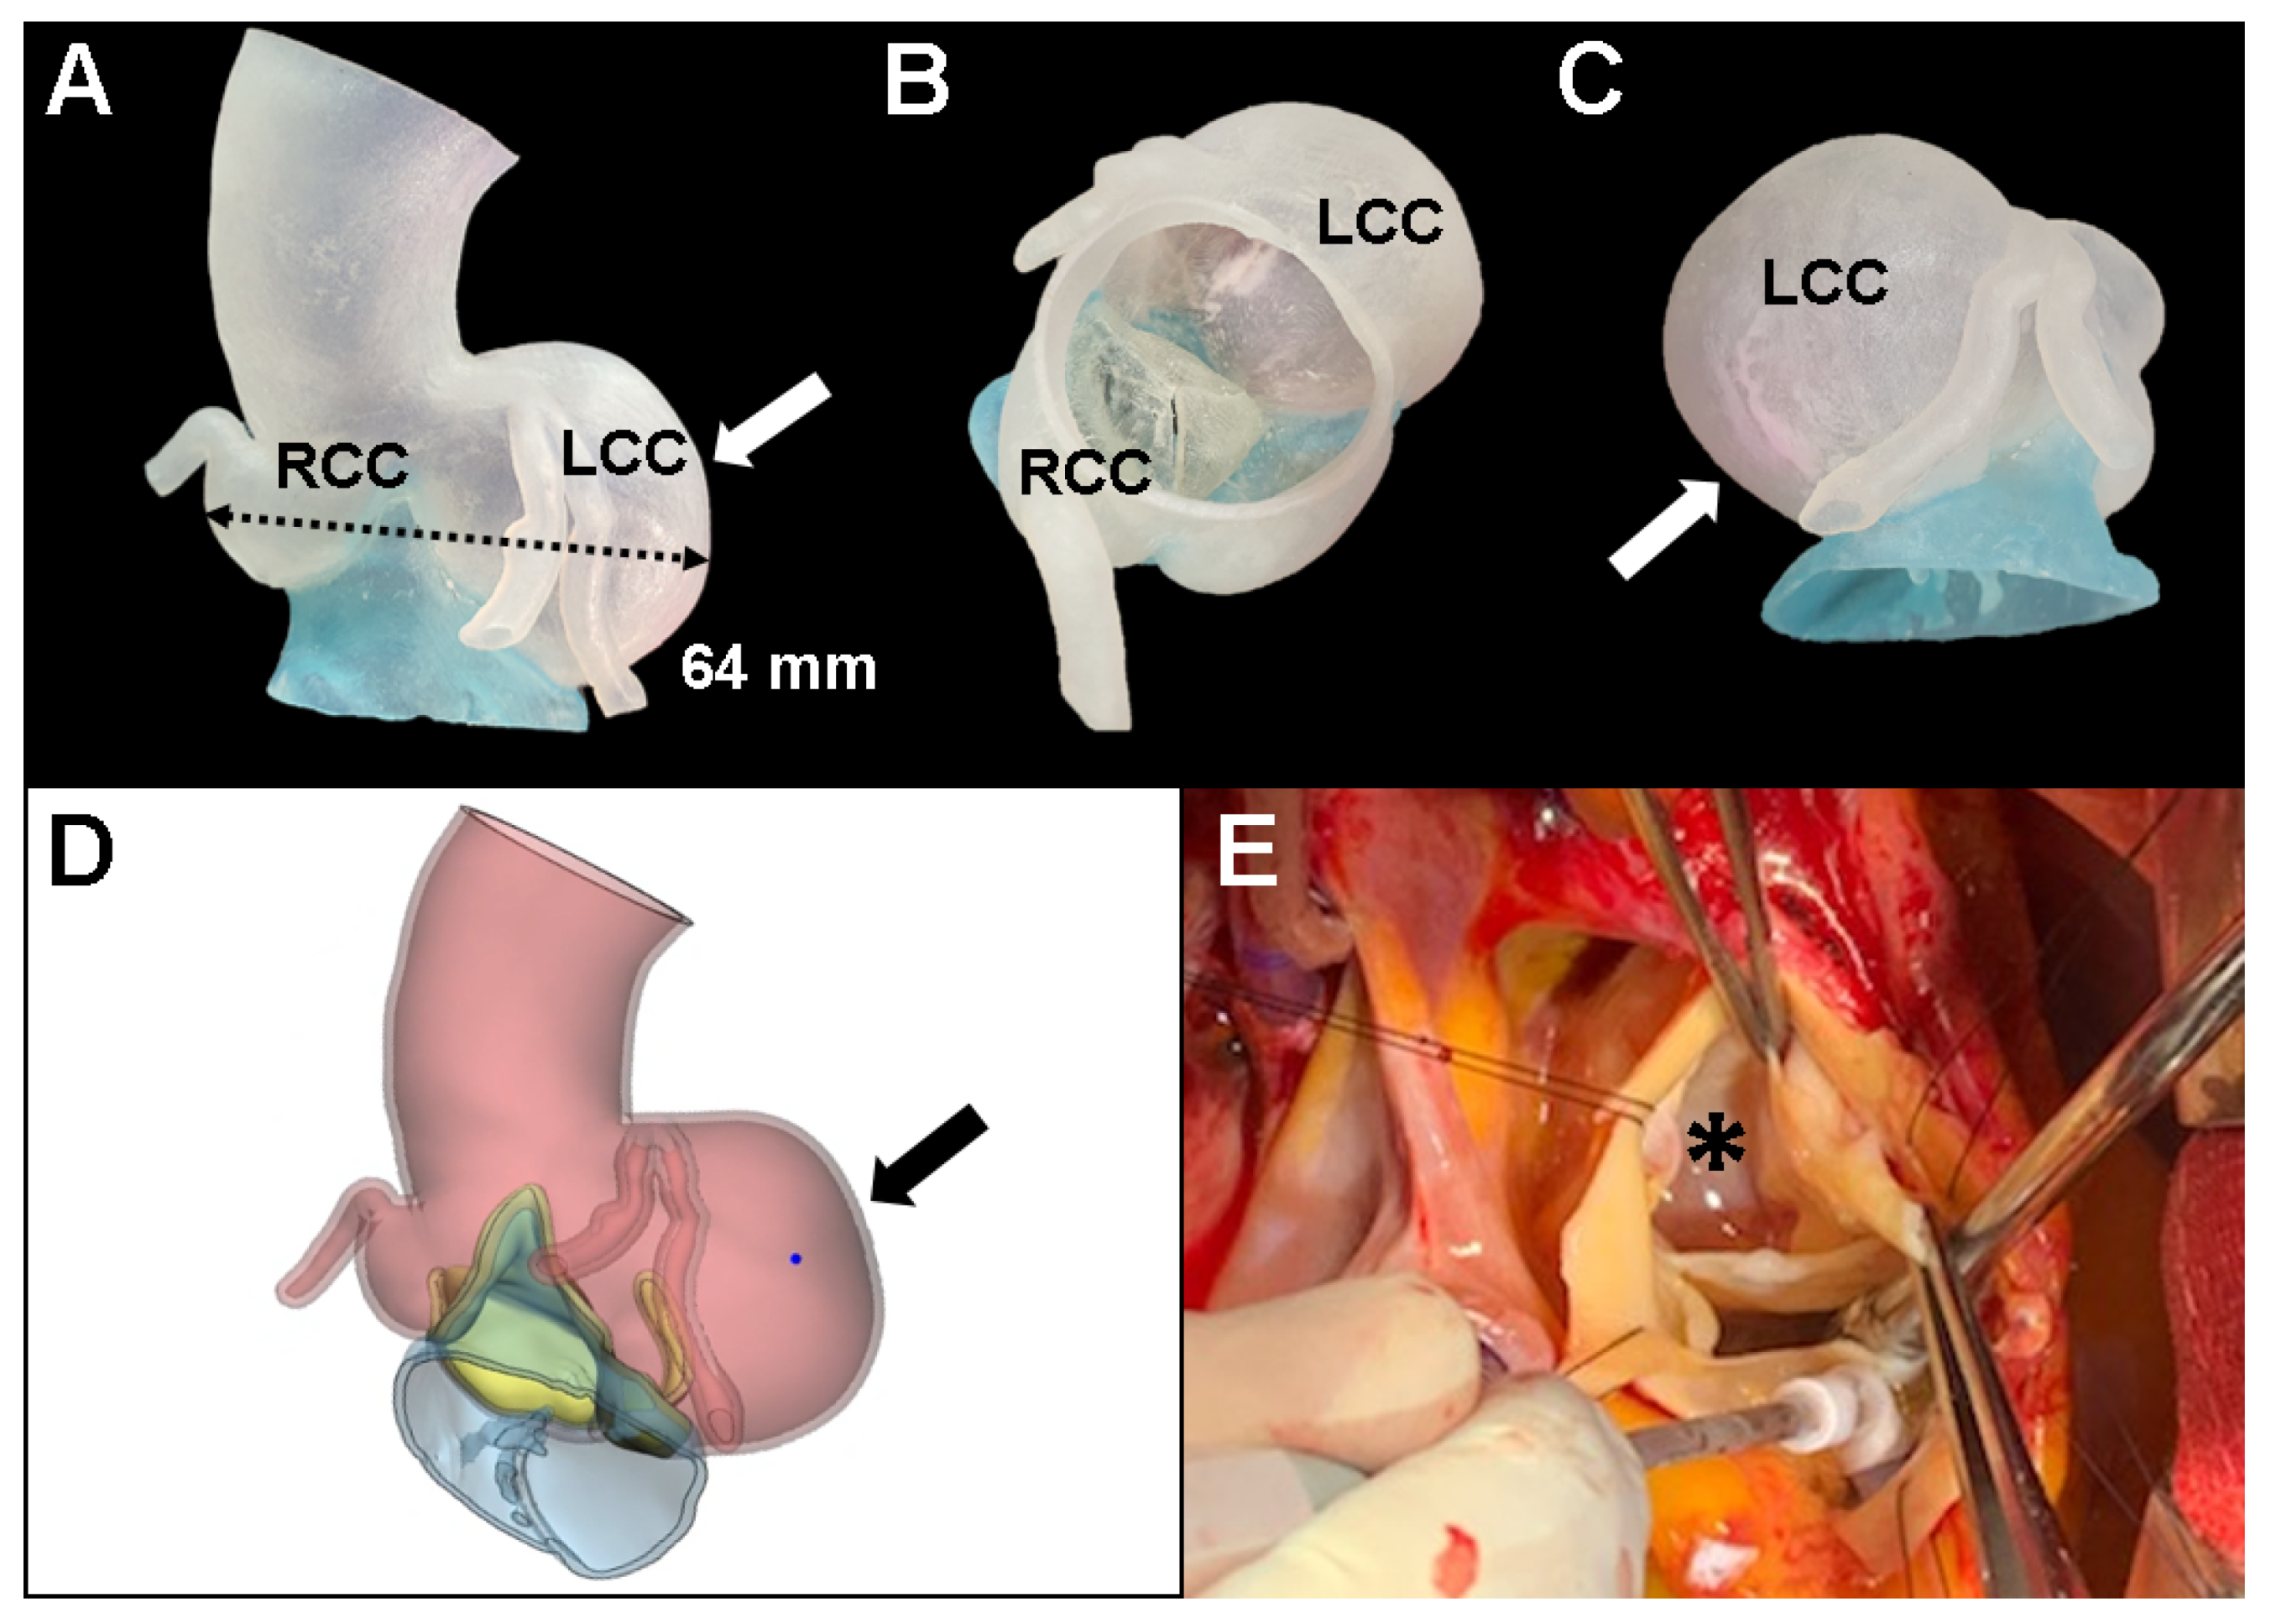

2. Case Presentation

3. Discussion